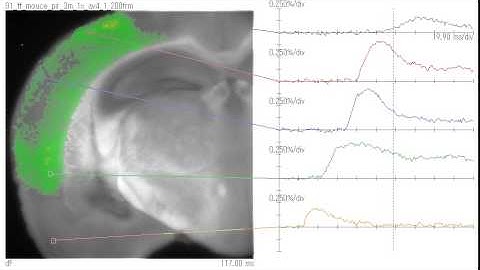

Improved adult brain slice method, Ca imaging (cortex).wmv